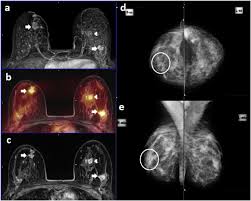

Aggressive Or Slow Growing Tumor Contrast Agent Gives Clues Healthcare In Europe Com from healthcare-in-europe.com You may notice dimpling or pitting, and the skin on your breast. (1) gary ulaner, md, phd, facnm. A rash isn't the only visual symptom of inflammatory breast cancer. Embedded video for what does cancer look like? Some benign conditions such as fibrocystic disease can look like cancer. Four of eight patients in whom a loss of fatty hilum was seen in an axillary node on mri were found to have cancerous lymph nodes at the time of their breast surgery. Tumor size is an important factor in breast cancer staging, and it can affect a person's treatment options and outlook. On the flip side, there are benign (not cancerous) breast changes which can mimic breast cancer as well.

If these tests don't answer the quest. But not every woman who has been diagnosed with breast cancer needs a breast mri. Determining the extent of cancer after a new breast cancer diagnosis. It can also help detect breast cancer in women with breast implants and in younger women who tend to have dense breast tissue. An mri can be used to look for a disease, such as breast cancer. But there are also other reasons to have a breast mri. Inflammatory breast cancer affects breast tissue and can appear unusually dimpled or thick. Breast mri images are combined, using a computer, to create detailed pictures. A waiver of informed consent Mri scan is also used in breast screening for young women who are at higher risk of developing cancer. Dcis on mri may create an area of irregular enhancement of the mri dye into the breast. They're often easy to move around (mobile) and may be tender. A breast mri is a highly effective test.

Breast mri is sometimes used in women who already have been diagnosed with breast cancer, to help measure the size of the cancer, look for other tumors in the breast, and to check for tumors in the opposite breast.

They might be at higher risk due to having family members with cancer or because they have certain gene abnormalities (mutations). By comparison, only 11 out of 48 patients, or 23 percent, with all fatty hilum in place had cancer. Because the dye can affect the kidneys, your doctor may. Unlike traditional forms of breast cancer, inflammatory breast cancers do not develop unusual lumps within the affected breast. Magnetic resonance imaging (mri) of the breast — or breast mri — is a test used to detect breast cancer and other abnormalities in the breast. Mri of breast can help breast cancer diagnosis. When women undergo mris to check for breast cancer, the scans sometimes reveal suspicious masses elsewhere in the body, which can generate a lot of anxiety and require more testing. This means that the test finds a mass or other change that seems to show cancer but it is not cancer. A breast mri is a highly effective test. Palpation of benign breast masses. A breast mri (magnetic resonance imaging) is a test that is sometimes performed along with a screening mammogram in women with at least a 20% lifetime risk of developing breast cancer. You may notice dimpling or pitting, and the skin on your breast. Some benign conditions such as fibrocystic disease can look like cancer.

The Radiology Assistant Mri Of The Breast from radiologyassistant.nl Your doctor may recommend a breast mri for the following: A breast mri captures multiple images of your breast. This is why we ask questions about menstrual cycle and hormone therapies prior to your study. What does breast cancer look like on a mammogram? Dcis on mri may create an area of irregular enhancement of the mri dye into the breast. The features of a malignant breast condition on mri scan are often to do with the outer irregular borders of a lesion. An mri can be used to look for a disease, such as breast cancer. If you are at risk of getting a certain disease, your caregiver may want to do an mri to look for signs of the disease.